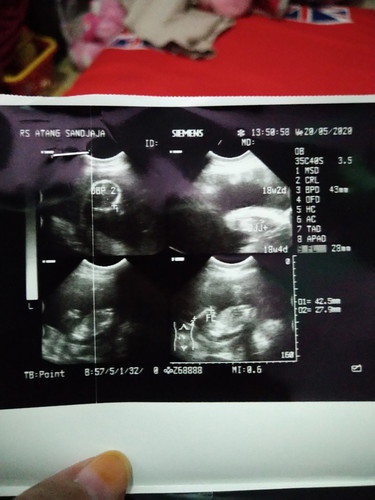

Semalem baru USG usia 28week .. Karna udah 2 hari gerakan nya agak berkurang (mungkin saya nya ga terasa karna akhir² ini aktifkan agak padet) langsung USG biar tenang.. Dan setelah d USG alhamdulillah sehat semua hasil nya bagus semua.. (Hamil yg ini agak parno hehe karna hamil yg kedua bertahan di 22 minggu meninggal dlm kandungan dan kembar) Oya saya 3 tahun lalu oprasi caesar,, hasil USG semalem dinding rahim nya bagus ketebalan nya jadi dokter nyaranin saya untuk normal (VBAC) .. Tapi Posisi bayi masih sungsang semoga cepet muter lagi bayi supaya bisa normal.. Sebenarnya cara apa saja yg penting sehat dan lancar.. Mohon doa nya yah biar di lancarkan semua nya.. Dan Semoga para bumil disini lancar² yah semua nya ☺ Oya Ada yg udah ngalamin VBAC kah disini ? Note : hamil pertama normal, kedua Caesar di 22week .. #bantusharing